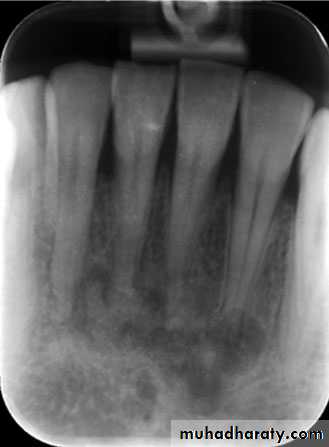

Location: posterior body of the mandible.

Periphery: ill defined with gradual transition to normal trabeculae.

Internal structure: *Decrease in bone density.

* Loss of trabecular sharpness.

*Scattered areas of radiolucency.

* Sclerotic regions → sequestra.

Effect on surrounding structures:

*Bone resorption or bone formation.*Bone formation is parallel to bone surface and lift the periosteum.

*A radiolucent band separates this periosteal new

bone from the bone surface.

This is continue to form several radiopaque lines

separated by radiolucent bands (Onion-skin

appearance) → Proliferative periostitis